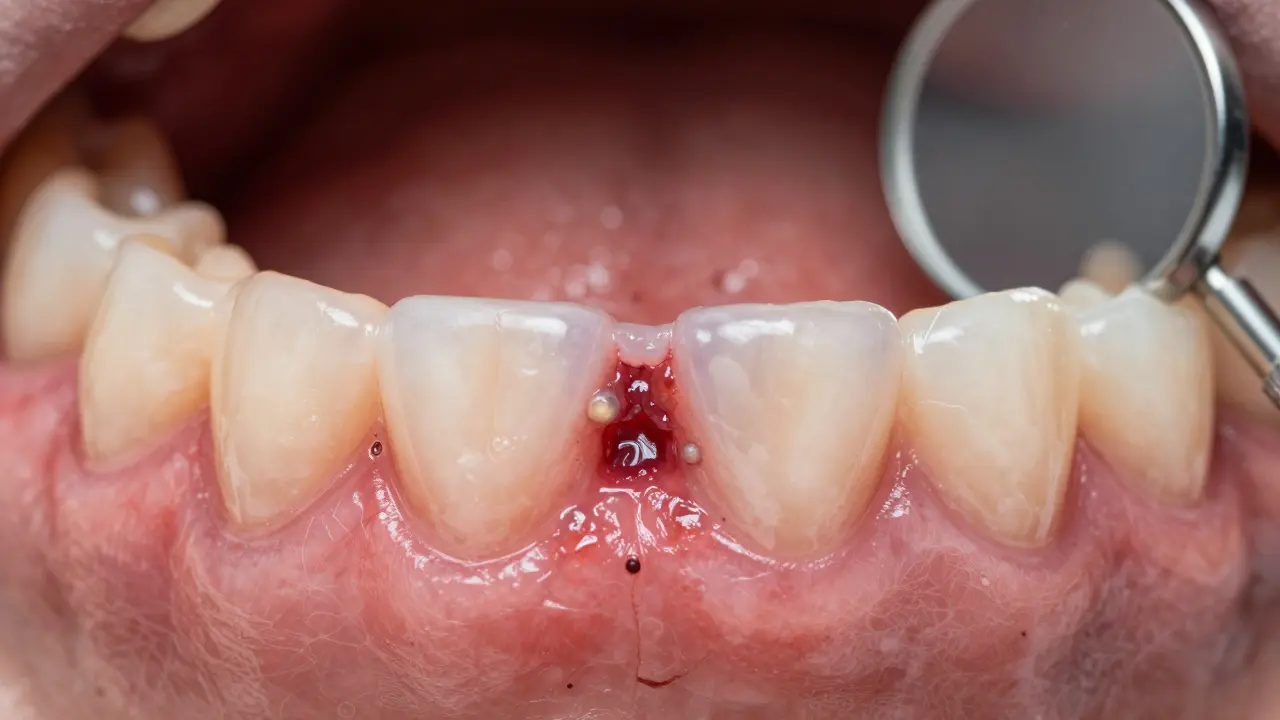

Kdy se zatahne díra po extrakci zubu? Co očekávat a kdy se obrátit na lékaře

Díra po extrakci zubu se zatáhne obvykle za 7-14 dní, ale úplné hojení kosti trvá až 6 měsíců. Zjistěte, co je normální, kdy se obrátit na lékaře a jak podpořit hojení.